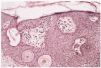

Se trata de un hombre de 41 años de edad que acudió a nuestro servicio por presentar desde hacía 10 años lesiones en forma de placas eritematosas infiltradas en regiones axilares, pectorales, hipogástrica y lumbosacra. El paciente fue diagnosticado de micosis fungoide a partir de los hallazgos clínicos e histopatológicos. A la exploración física presentaba en zonas axilares, pectorales, hipogástrica y lumbosacra placas eritematosas, con escaso componente epidérmico, mal delimitadas e infiltradas a la palpación. Llamaba la atención la existencia en el tronco de múltiples pápulas hiperpigmentadas, de superficie queratósica, que clínicamente correspondían a queratosis seborreicas y que eran más numerosas sobre las placas eritematosas que sobre la piel normal (fig. 1). Se tomó biopsia de una de las lesiones queratósicas que se encontraban sobre las placas eritematosas. La histología mostraba una lesión típica de queratosis seborreica infiltrada por linfocitos T de micosis fungoide (fig. 2).

Fig. 2.--Linfocitos de pequeño tamaño con halo claro que infiltran la epidermis de una queratosis seborreica (hematoxilina-eosina, x40).